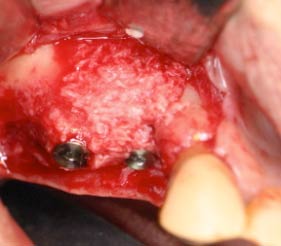

2) 比較的広い範囲の欠損(ブロック移植)

骨をブロックで採取し、チタンのネジで止めます。骨採取にかかる時間は15-20分 です。